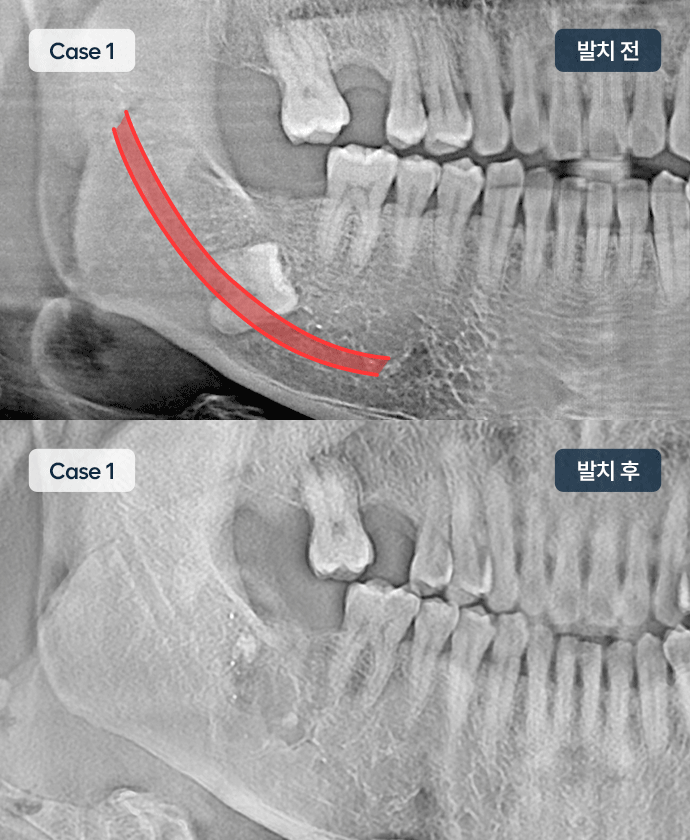

사랑니 발치

사랑니는 치아 가장 깊숙이 자리잡고 있어 양치가 안되는 경우가 많습니다.

이 경우 충치가 옆 어금니까지 번져, 어금니 발치 후 임플란트를 하는 경우도 종종 있어 관리가 필요합니다.

특히 매복인 경우, 신경에 가깝게 자리할 때가 있어 수술시 주의가 필요합니다.

대학병원 추천 케이스

매복 사랑니· 치아 발치